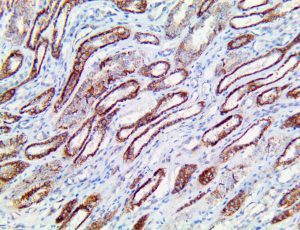

Clinical and laboratory manifestations of HLH include fever, enlarged liver and/or spleen, neurologic dysfunction, coagulopathy, liver dysfunction, cytopenias (i.e., low levels of erythrocytes, leukocytes, and/or platelets), hypertriglyceridemia, hyperferritinemia, hemophagocytosis, and eventually diminished NK cell activity as the immune system becomes progressively paralyzed. HLH can be familial (primary HLH) or secondary to another disease process (sHLH), such as rheumatic disease, in which it is referred to as macrophage activation syndrome (MAS, characterized by elevated ferritin).

This activation induces inflammatory monocytes to highly express IL-6, starting a localized and then systemic cascade effect that results in hyperproduction of IL-6, which accelerates the inflammatory process. Because IL-6 also increases vascular permeability, excessive levels cause blood vessels to become very leaky. This, along with clotting factors released from vascular endothelial cells, stimulates the coagulation cascade, resulting in microthrombosis (tiny clots), which leads to ischemia and tissue death of the kidney, intestines, heart, liver, brain and extremities.